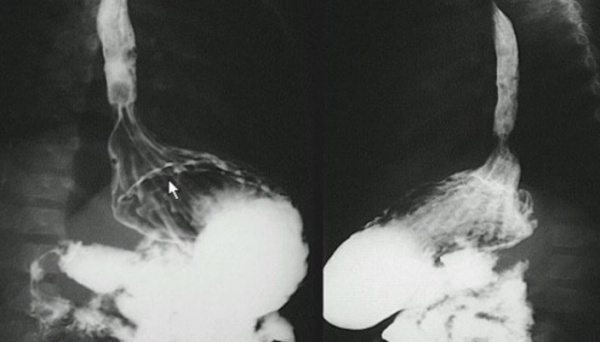

Типичные изменения, выявляемые в пищеводе при рентгеноскопии с барием:

а Стеноз, развившийся после ожога щелочью.

б Тракционный дивертикул.

в Пульсионный дивертикул.

г Ахалазия пищевода в сочетании с мегаэзофагусом.

д Идиопатический спазм пищевода.

е Варикозное расширение вен пищевода.

ж Сдавление пищевода извне.

з Доброкачественная опухоль, выступающая в просвет.

и Рак пищевода.

к Трахеопищеводный свищ в виде буквы «Н».